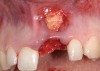

A 39-year-old woman presented with a failing endodontically treated maxillary right central incisor. Clinical and radiographic examination revealed a thick, flat periodontal biotype, high smile line, and a fistulous tract of the labial vestibule opposite the incisor (Figure 16 and Figure 17). Also noted post-extraction was a thin (< 2 mm) labial plate with 8 mm of vertical bone loss (Figure 18). Treatment consisted of a conservative flapless extraction with placement of a free connective tissue graft (Figure 19) sutured through the socket, along with placement of a bone mineralized allograft (MinerOss) (Figure 20 and Figure 21). Five months post-extraction, a root-form implant was placed, nonsubmerged, along with a bovine bone xenograft as a veneer into a sub-periosteal labial pouch (Figure 22 through Figure 24). A provisional crown was placed 3 months later, allowing for adequate soft-tissue grooming (Figure 25).

Figure 18  Post-extraction socket defect with loss of labial plate.

Figure 18